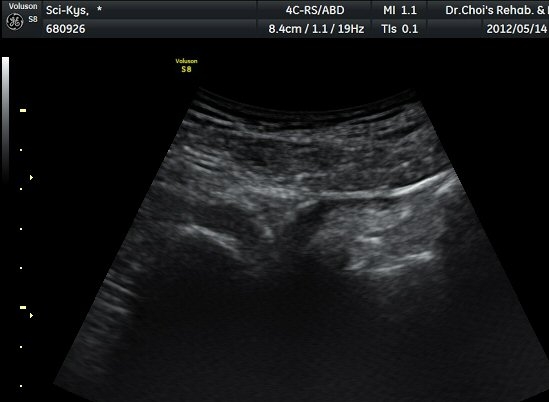

Á¤»óÃø(±×¸² 6, 7)°ú ºñ±³Çϸé Á°ñ½Å°æÀÇ ³»Ãø ÀüÀ§°¡ ¶Ñ·ÈÇÏ´Ù.

ŽÃËÀÚ¸¦ ¾à°£ ±ÙÀ§ºÎ·Î À̵¿ÇÏ´Ï °æ°è°¡ ºÒºÐ¸íÇÑ »À°¡ Á°ñ½Å°æ ¿ÜÃø¿¡¼­ µ¹ÃâÇϸ鼭

Á°ñ½Å°æÀ» ³»ÃøÀ¸·Î ½ÉÇÏ°Ô ÀüÀ§½ÃŲ´Ù(±×¸² 4, 5).